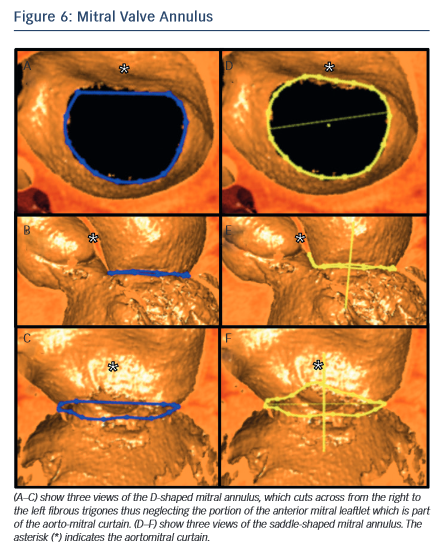

In the context of transcatheter mitral valve replacement (TMVR), MSCT has been proposed to quantify the mitral valve annulus. The mitral valve annulus is often described as either saddle-shaped or as D-shaped (see Figure 6). It has been argued that for some of the devices, in particular those that are not axially symmetrical, the D-shaped annulus may be more appropriate for sizing purposes.59,60 This question remains to be studied, but in the interim we suggest that both techniques be Image titleemployed.